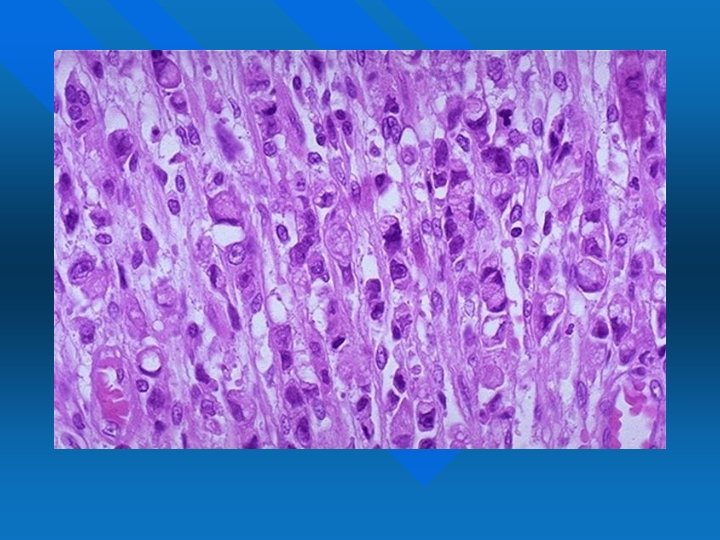

LEIOMIOSARCOMI Rispetto al corrispettivo benigno, il leiomiosarcoma è di dimensioni maggiori e mostra figure chiaramente anaplastiche n Marcato pleomorfismo nucleare, cellule giganti e figure mitotiche talora mostruose n Necrosi intratumorale, foci emorragiche, alto indice mitotico n